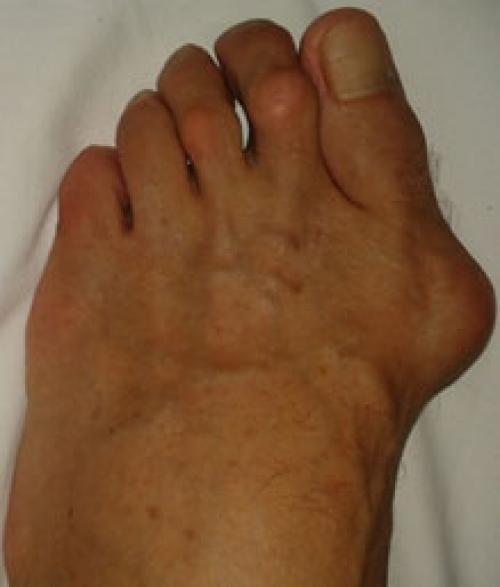

Симптомы стопы портного. В первую очередь обращает на себя внимание косметическая деформация 5 пальца, наличие «шишки» в области его основания, формирование мозоли. Пациенты часто жалуются на боли в данной области, особенно беспокоящие их при ношении обуви с узким мысом.

При осмотре необходимо оценить ширину переднего отдела ступни, наличие гиперкератоза по наружной поверхности. Амплитуда движений 5 плюсне-фалангового сустава при этом часто остаётся нормальной.

Варусная деформация 5-го пальца (деформация тейлора) – патологическое состояние, при котором V палец отклоняется внутрь, а плюсневая кость кнаружи, появляется шишка у основания V пальца.

Симптомы

- дискомфорт, ноющая боль в области головки пятого плюснефалангового сустава;

- воспаление окружающих головку плюсневой кости мягких тканей, развития бурсита, омозолелости;

- “шишка” в области головки 5-й плюсневой кости.